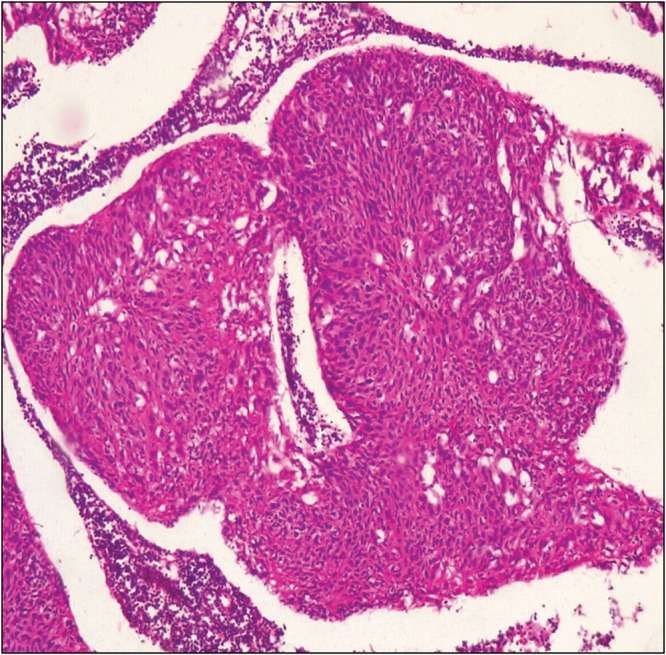

Ocular surface squamous cell neoplasia can arise from a premalignant lesion (conjunctival intraepithelial neoplasia or ocular surface squamous cell intraepithelial neoplasia). Their respective magnitudes will provide an indication of early treatment or progression of the disease. This study, therefore, aims to determine the frequency of premalignant and malignant ocular surface squamous neoplasia. This is a retrospective study of all cases of premalignant and malignant ocular surface squamous neoplastic lesions histologically diagnosed over an 18-year period at the Department of Anatomic Pathology, University of Benin Teaching Hospital. The results showed that there were more malignant ocular surface squamous neoplastic lesions relative to ocular surface squamous cell intraepithelial neoplastic lesions. Also, the latter occurs at a relatively lower median age in comparison to the former. In conclusion, our findings suggest that late presentation of symptoms may account for higher frequency of malignant ocular surface squamous neoplastic lesions.